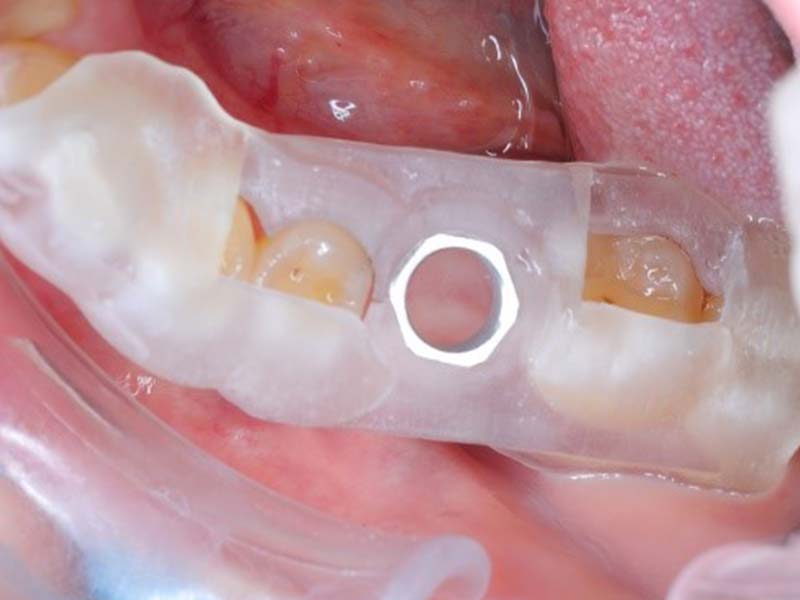

利用CT影像及口掃檔清楚掌握患者口腔內骨頭、牙齒、神經與血管的位置,事前模擬植體位置,並利用 3D 列印做出手術導板,確保植入深度與位置都恰如其分,在手術中能控制植體精準的位置與深度,避免傷及神經血管、打穿鼻竇,又足以讓齒槽骨牢牢地抓住人工牙根。

數位導板結合了電腦斷層分析,能較瞭解骨頭狀況、神經及鼻竇的位置,大幅提高植體放置的精準度,也配合掃描儀將患者齒列狀況輸入電腦,設計未來贋復的位置,增加手術的成功率。最後利用3D列印機產出導板,只要喝杯咖啡的時間就印好了,提高了工作效能。